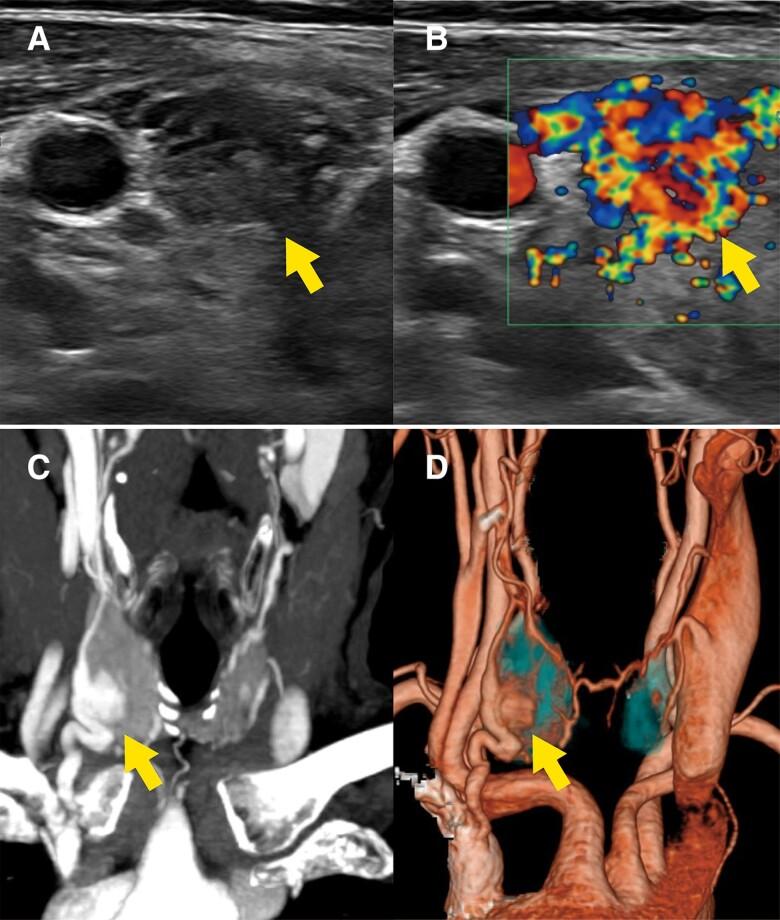

Hereditary hemorrhagic telangiectasia (HHT) causes arteriovenous malformations (AVMs) in several organs. This report is the first to document and image a thyroid AVM complication in HHT. A 72-year-old woman with HHT was referred for thyroid nodule evaluation. Ultrasonography showed a hypervascularized nodule in the right thyroid lobe which was initially suspected to be malignant. However, 3-dimensional computed tomography angiography demonstrated a thyroid AVM with abnormal anastomosis of the superior thyroid artery and the inferior thyroid vein. In the formation of thyroid AVM, here, chronic thyroiditis and hypothyroidism complications may have been a second hit, due to the predisposing first-hit germline mutation. This report sheds light on overlooked thyroid lesions in HHT and advocates a noninvasive imaging approach in diagnosing thyroid AVMs. Furthermore, this case suggests a potential mechanism of AVM formation in human HHT, possibly supporting the second-hit hypothesis.

遗传性出血性毛细血管扩张症(HHT)可导致多个器官出现动静脉畸形(AVM)。本报告首次记录并成像了HHT患者的甲状腺AVM并发症。一名72岁的HHT女性因甲状腺结节评估前来就诊。超声检查显示右甲状腺叶有一个血管丰富的结节,最初怀疑为恶性。然而,三维计算机断层血管造影显示为甲状腺AVM,甲状腺上动脉与甲状腺下静脉存在异常吻合。在甲状腺AVM的形成过程中,由于最初的胚系突变易感性,慢性甲状腺炎和甲状腺功能减退并发症可能是第二次打击。本报告揭示了HHT中被忽视的甲状腺病变,并提倡采用非侵入性成像方法诊断甲状腺AVM。此外,该病例提示了人类HHT中AVM形成的潜在机制,可能支持二次打击假说。